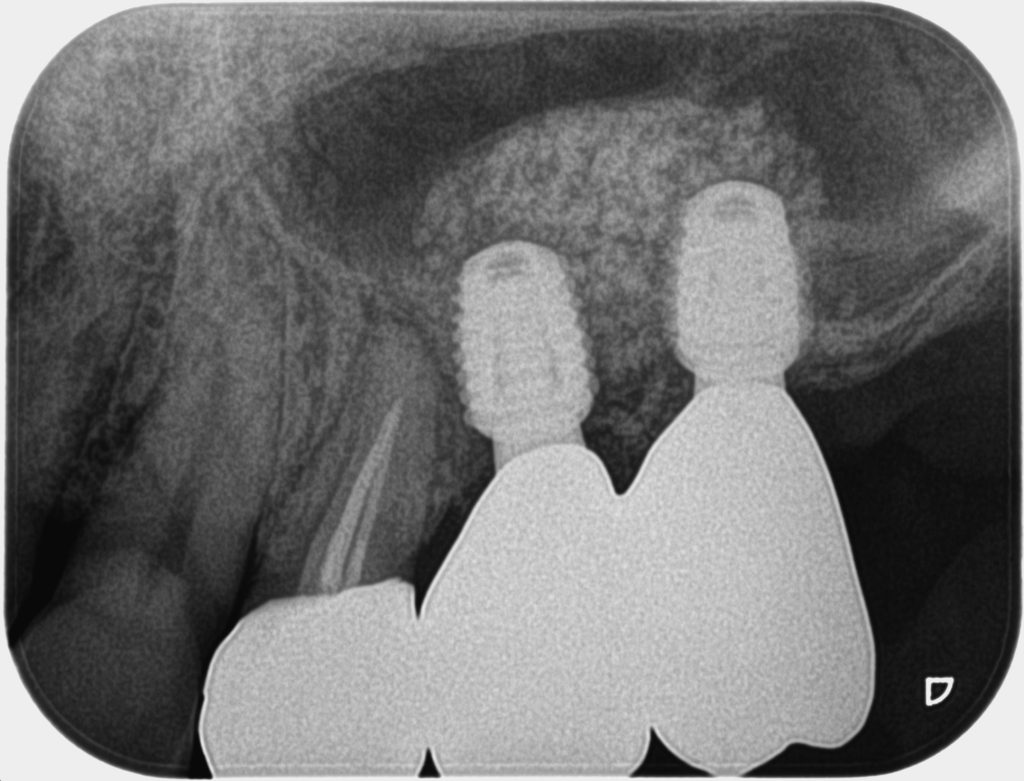

症例250代 男性 歯根破折にて右上5番を抜歯

治療前

ブリッジ・義歯・インプラントの選択肢を提案。

力学的に強く、両隣在歯に負担のかからないインプラントを選択。

ソケットリフト(上顎洞洞底膜挙上術)を行い、骨の高さを確保しインプラントを埋入。

オペ後、骨との密着値も良く、約3ヶ月後にはジルコニアを装着し終了。

リスクとしては外科的侵襲がある。デメリットは、保険外診療の為、経済的負担がある。

費用 64万(税込)(オペ・仮歯・最終補綴物まで含む)